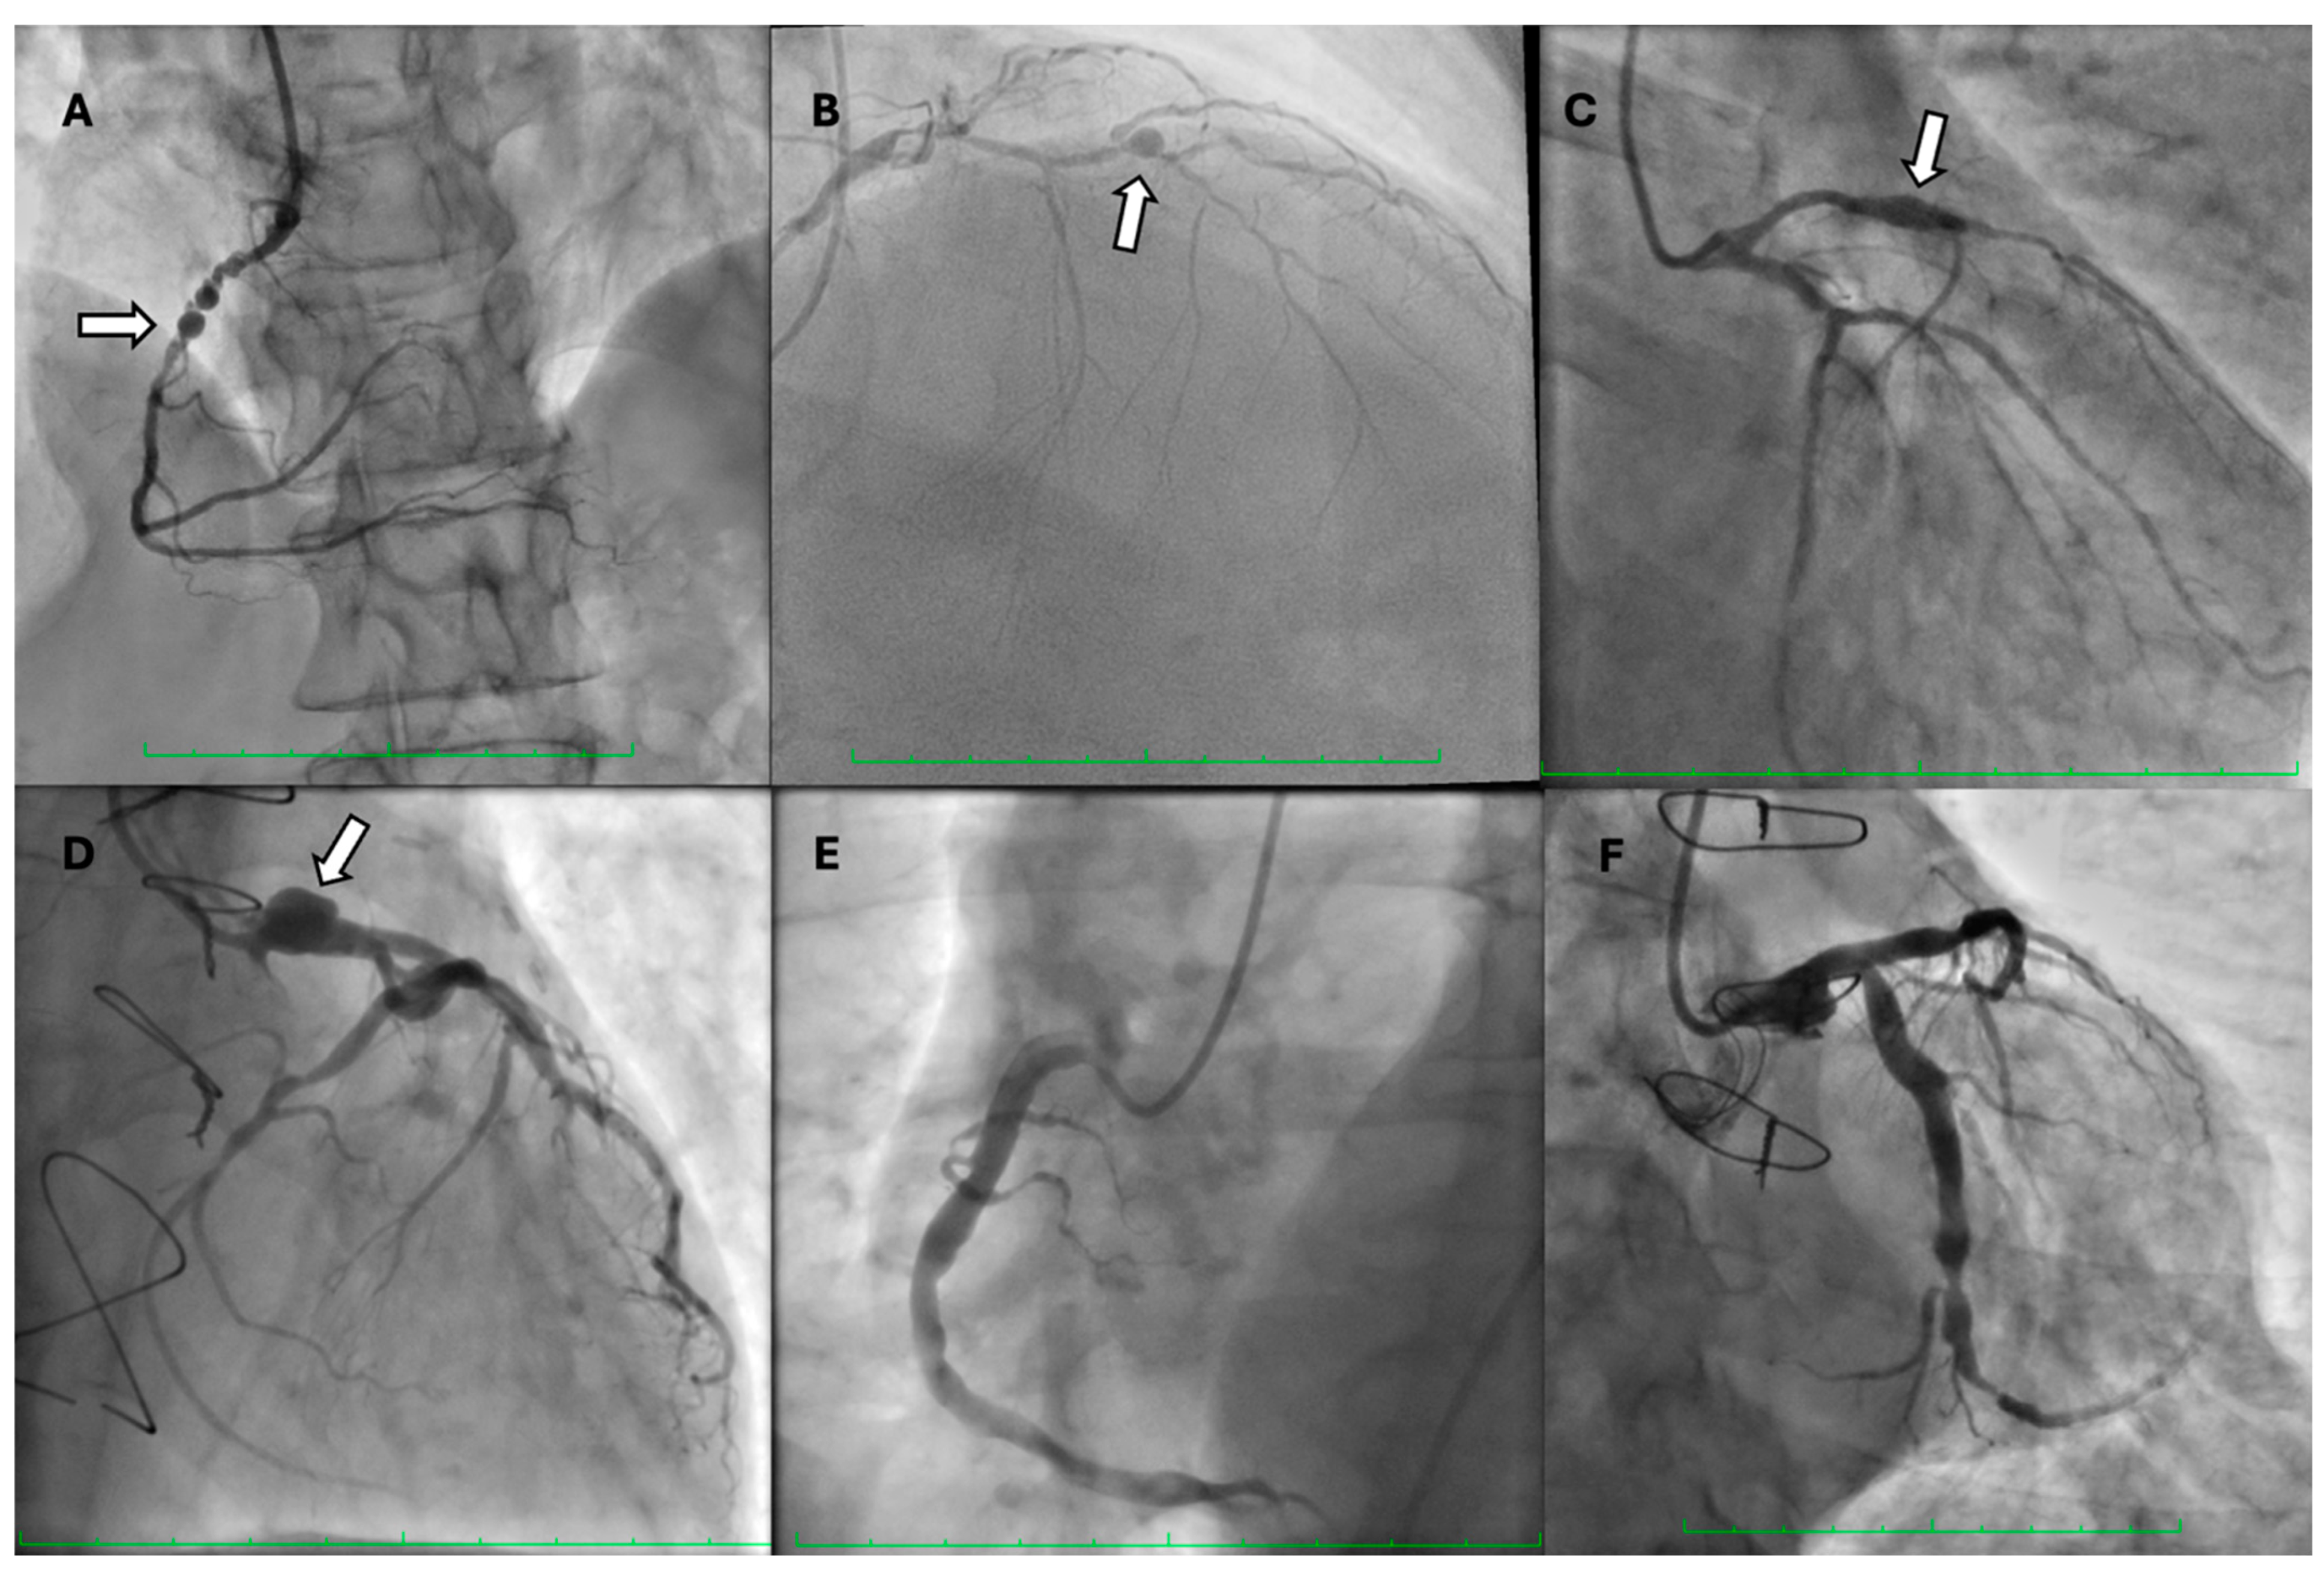

7. Prognosis

8.2. Invasive Treatment